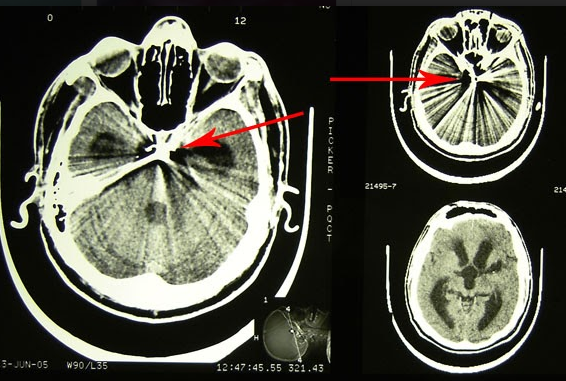

Tânărul a fost împușcat în regiunea temporo-parietală stânga, glontele rămânând intracerebral. Din spusele mamei, s-a întâmplat în Germania, unde tânărul își făcea studiile. Acesta s-a aflat în comă aproximativ trei luni jumate. Când și-a revenit prezenta afazie mixtă și lipsa vederii la ambii ochi. S-a tratat în România, iar la Chișinău pacientul a fost internat pentru investigații și tratament după ce în Germania și România a primit refuz de a fi operat din cauza gravității stării lui, pe motiv de prezența unui corp străin endocranian manifstat clinic prin retard mental, ataxie, ambliopie profundă bilaterală, pronunța doar unele silabe, dereglări de comportament, toate în evoluție stabilă, cu alterarea capacității de lucru și calității vieții pacientului.

„A fost foarte greu de localizat glontele. Nu exista încă neuronavigația. Am efectuat operația prin radiografia intraoperatorie. Cu greu am găsit glontele căci era amplasat în creier la o adâncime foarte mare. Succesul meu ca neurochirurg a fost nu doar extragerea glontelui dar și fapul că pacientul după operație putea sta în picioare, putea sta așezat, a început să perceapă unele comenzi de la cei apropiați iar când l-am externat mi-a dat mâna și și-a luat rămas bun. Bucuria mea a fost că tânărul a venit la Chișinău fiind adus pe targă dar a plecat stând așezat în mașină,” a mărturisit directorul INN, Grigore Zapuhlîh.

Starea după înlăturarea glontelui endocranian prin abord supraorbital stânga era satisfăcătoare, în ameliorare cu prezența mișcărilor spontane în toate extremitățile. Glontele a fost extras cu success fără apariția conplicațiilor neurologice. În două săptămâni pacientul fiind externat.